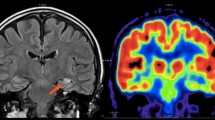

An 18-year-old male with drug-resistant epilepsy. a Axial FLAIR image shows hypomyelination and indistinctness of the gray-white matter junction throughout the left cerebral hemisphere (arrows). b–c Axial FDG-PET reveals diffuse left hemisphere hypometabolism (arrows) related to extensive developmental cortical malformations. These malformations were overlooked in the two prior MRI examinations, likely due to diffuse involvement